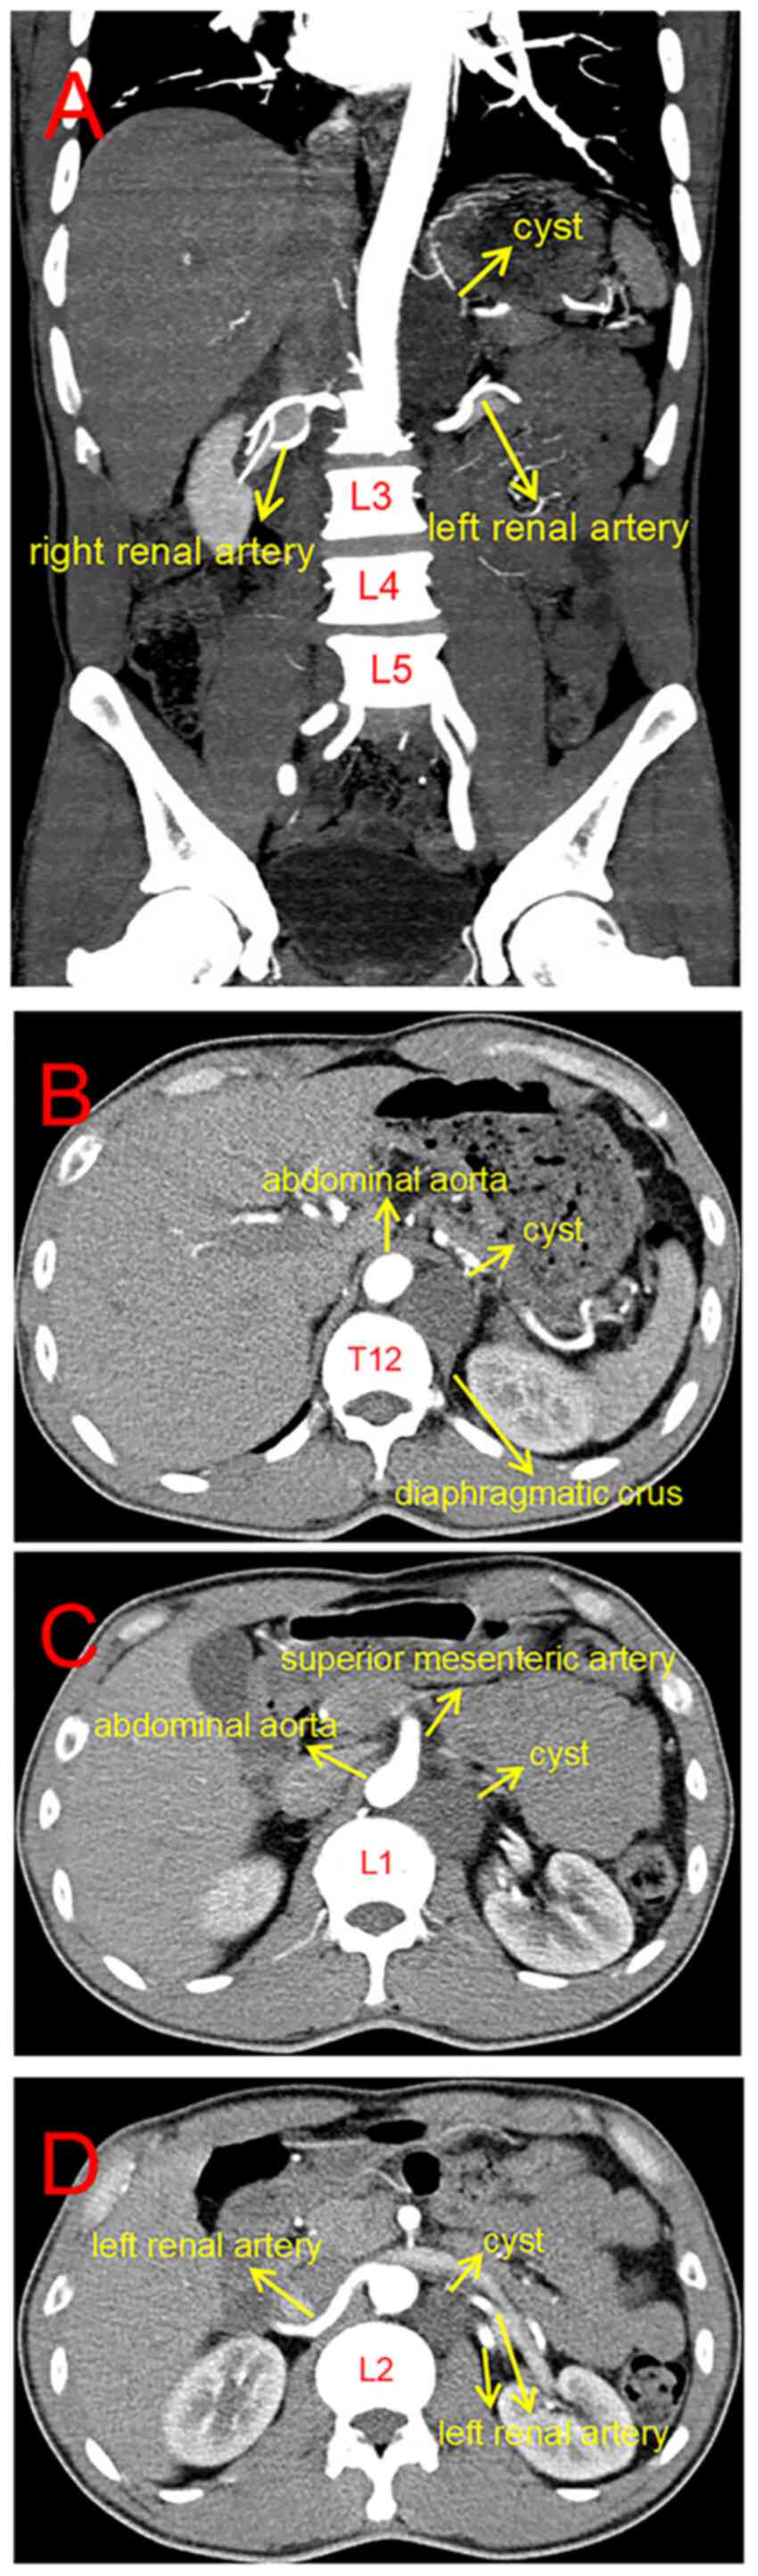

CT angiography of the abdominal aorta (Siemens Sensation 16;

Siemens AG) revealed that there was a low-density cystic mass with

a Hounsfield units value of 30 originating from the left diaphragm

foot on the left front of the T12-L2, mildly compressing the aorta.

The size of the cyst was ~3x4x6 cm (Fig. 1A). There was no change in the

density of the cyst in all images. The upper segment of the cyst

was in the retrocrural space, whereas the lower segment was in the

retroperitoneal space (Fig. 1B-D).